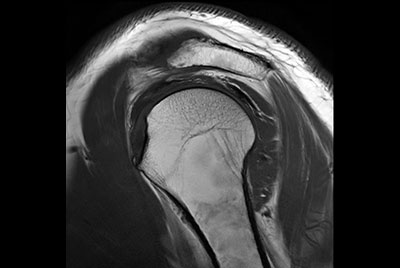

Push-button Shoulder exam, under 5 minutes

High resolution imaging with the dS 16ch Shoulder coil and Compressed SENSE

Routine shoulder imaging

High resolution shoulder imaging

Shoulder with the dS Shoulder 16ch coil

Shoulder imaging

Motion-free MR Arthrogram shoulder imaging

Motion-free Shoulder imaging

Shoulder imaging using ComforTone

Shoulder imaging with dS Flex coil